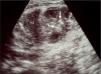

En la ecografía abdominal realizada al ingreso se observó un riñón izquierdo aumentado de tamaño, en el que llamaban la atención pequeñas áreas ecogénicas en la unión corticomedular, así como una mala definición de las pirámides renales. En el área suprarrenal izquierda se apreciaba una colección líquida de 42 × 25mm de tamaño, que afectaba a la porción medular de la glándula, compatible con hemorragia suprarrenal (fig. 1). En la ecografía Doppler pulsada y en color se evidenció la ausencia total de flujo en la vena renal izquierda (fig. 2). No se pudo valorar la vena cava en esta confluencia anatómica por la existencia de artefactos.